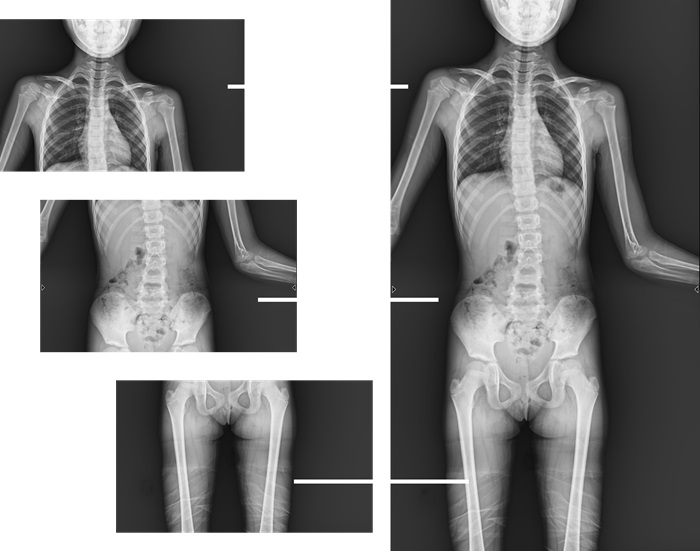

與此同時(shí),普利德動(dòng)態(tài)平板DRF還具有全身拼接功能,尤其適用于全脊柱和全下肢攝影,為臨床提供高精度圖像,輔助脊柱畸形矯形治療、康復(fù)檢查。

而且,影像采集幅面大,17×17英寸超大視野可覆蓋成年人的全胸全腹,并且能在連續(xù)動(dòng)態(tài)中實(shí)時(shí)高清點(diǎn)片,從而達(dá)到精準(zhǔn)診斷的目的。設(shè)備靈活高效的多維度運(yùn)動(dòng)設(shè)計(jì),也帶來(lái)了更加智能化、人性化操作體驗(yàn),可大幅提升檢查效率。